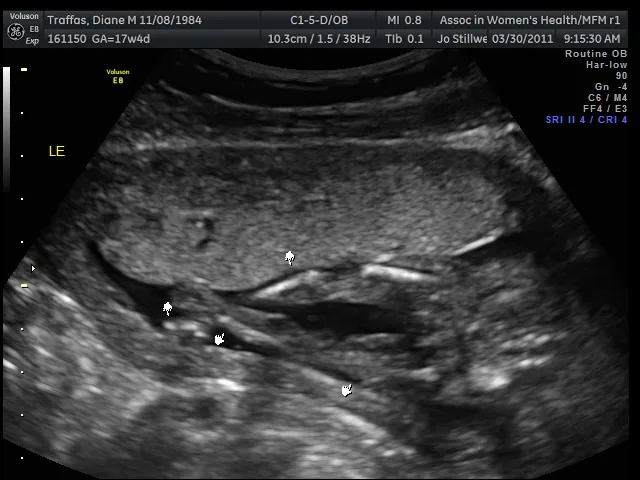

As promised, here are the sonogram images and video of our son. Thanks to everyone who assumed that our announcement was an April Fools’ scheme – you made our day!

As promised, here are the sonogram images and video of our son. Thanks to everyone who assumed that our announcement was an April Fools’ scheme – you made our day!